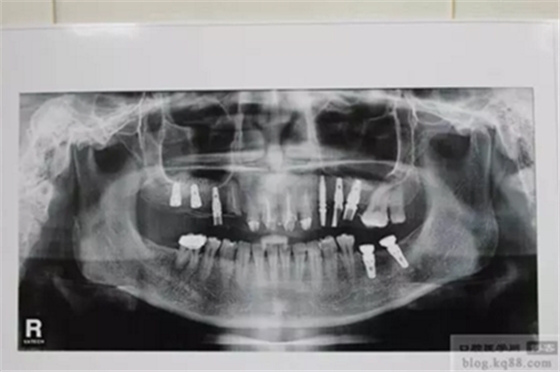

上前牙做充填和纖維樁修復(fù)后左上后牙內(nèi)提升植入三顆植體

右上后牙外提升

直接上基臺(tái)做臨時(shí)樹脂橋體,即刻負(fù)重

上圖為術(shù)后1年X光片 上基臺(tái)